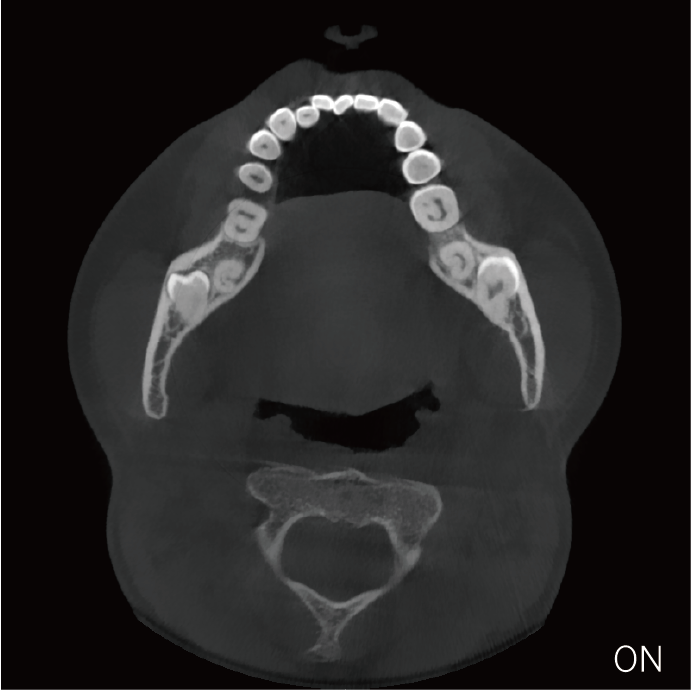

超能去伪 至臻影像

支持局部超清三维显示

可根据临床需求任意调整成像区域大小实现局部超清三维显示

临床样片